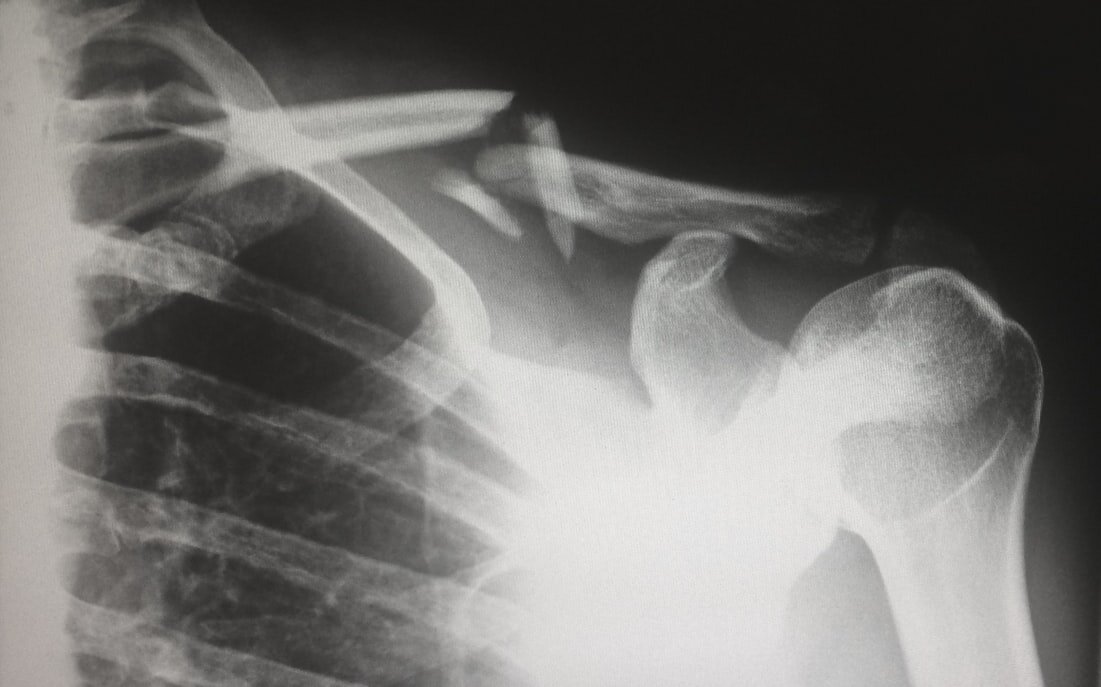

Гипсовая повязка при переломе, для чего она нужна?

При лечении переломов в первую очередь нужна иммобилизация конечности (фиксация), для этого за частую используют одно из лучших средств, гипсовую повязку. Такую повязку накладывают при переломах, на поврежденную часть тела для фиксации, и ускорения процесса восстановления. Гипсовая повязка после наложения будет высыхать, в некоторых случаях это занимает до 24 часов, при высыхании гипс выделяет тепло, что трудно будет не заметить. Продолжительность ношения такой повязки зависит от сложности травмы, и устанавливается только доктором) Как же ухаживать за такой повязкой? 1. Нельзя мочить. 2. Не снимать без разрешения доктора. 3. не опираться на повязку. 4. если бинт загрязнился, просто намотайте чистый) Обратитесь к доктору если: 1. Повязка сильно давит. 2. Боль и отёк не проходят после наложения повязки. 3. Гипс стал влажный и мягкий, или треснул. 4. Не приятный запах от гипса, и повышенная температура тела. Снятие гипсовой повязки : 1. Когда пойдете снимать гипсовую повязку с ноги, т